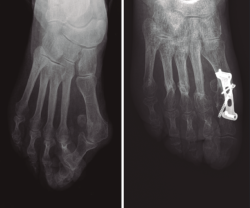

Clásicamente, se ha sugerido que en casos de HV severo, la artrodesis MTF es una opción quirúrgica que podría ser complementada con una osteotomía de la base del primer metatarsiano para cerrar el AIM(11). En la actualidad, es frecuente encontrar recurrencias del HV en pacientes tratados previamente con técnicas quirúrgicas que no han logrado la corrección del AIM. En pacientes con HV severo sin tratamiento previo y pacientes con recidivas de la deformidad tras cirugía, existe el dilema de cómo deben ser tratados. Una propuesta quirúrgica es la artrodesis MTF aislada(7,9,12) y, frente a este tratamiento, ha sido propuesto un tratamiento combinado (artrodesis MTF más osteotomía para reducción del AIM) (Figura 3).

Figura 3. Radiografía prequirúrgica (izquierda) de una paciente con hallux valgus severo. Radiografía posquirúrgica (derecha) de la misma paciente tratada mediante artrodesis metatarsofalángica asociada con una técnica de cierre del primer ángulo intermetatarsiano (osteotomía distal).

Sin embargo, para los/as autores/as de este trabajo y en función de su capacidad de reducción del AIM, la artrodesis MTF y el tratamiento combinado son en realidad tratamientos diferentes y, por lo tanto, deberían aplicarse en situaciones diferentes. Según los datos de este estudio, en casos con

HV severo y/o en recidivas de un tratamiento previo insuficiente (sin corrección del AIM) (Figura 4), el tratamiento combinado (artrodesis MTF más reducción del primer AIM) podría garantizar mejor un estrechamiento del antepié.

Figura 4. Radiografía prequirúrgica (izquierda) de una paciente con hallux valgus severo tratada previamente sin cierre del primer ángulo intermetatarsiano. Radiografía posquirúrgica (derecha) de la misma paciente tratada mediante artrodesis metatarsofalángica asociada con una técnica de cierre del primer ángulo intermetatarsiano (Lapidus).